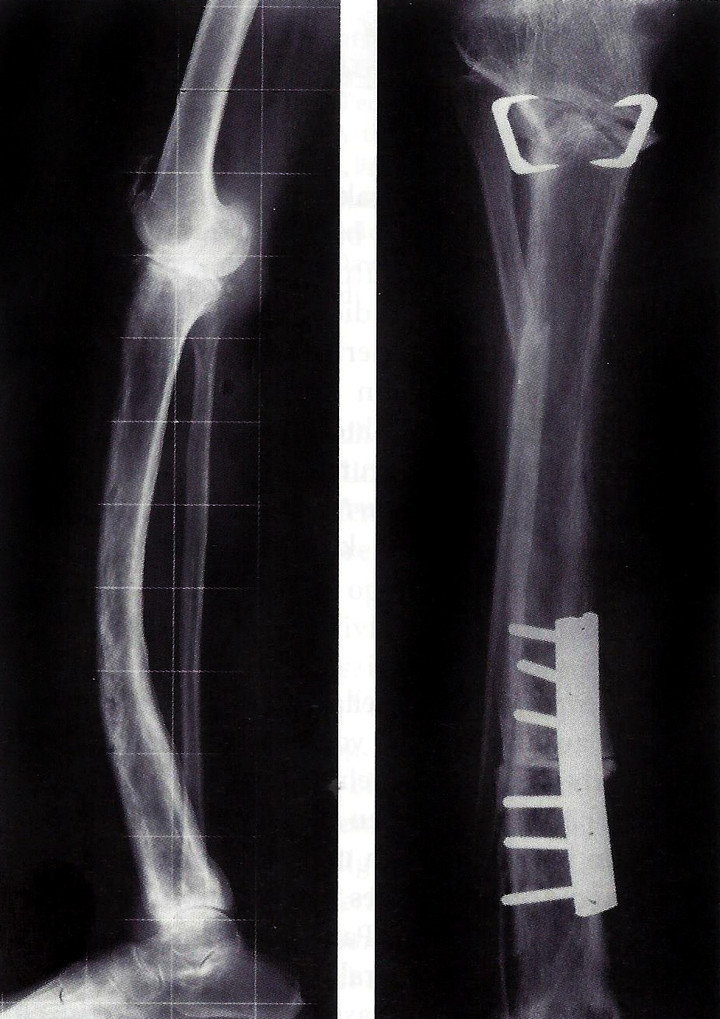

Im Februar, 6 Monate vor dem Abflug, wurde mir erstmals bewusst, wie anfällig und wie viele Komponenten mitspielen müssen, dass wir in Indien, 7000 km westlich von Europa entfernt, zu sechst auf einem Gipfel stehen können. Besonders klar wurde es mir, als mich Patrick anrief (der fünfte im Alpinkader Bunde) und mir mitteilte, dass er gerade mit einem gebrochenen Unterschenkel und samt 400 g Eisen bestückt im Krankenhaus liegt… Uff. Knapp ein halbes Jahr vor der Expedition mit so einer schweren Verletzung laborieren lies jeden, besonders die Ärzte skeptisch sein, ob Patrick mitfliegen bzw. die größere Herausforderung, mitgehen kann.